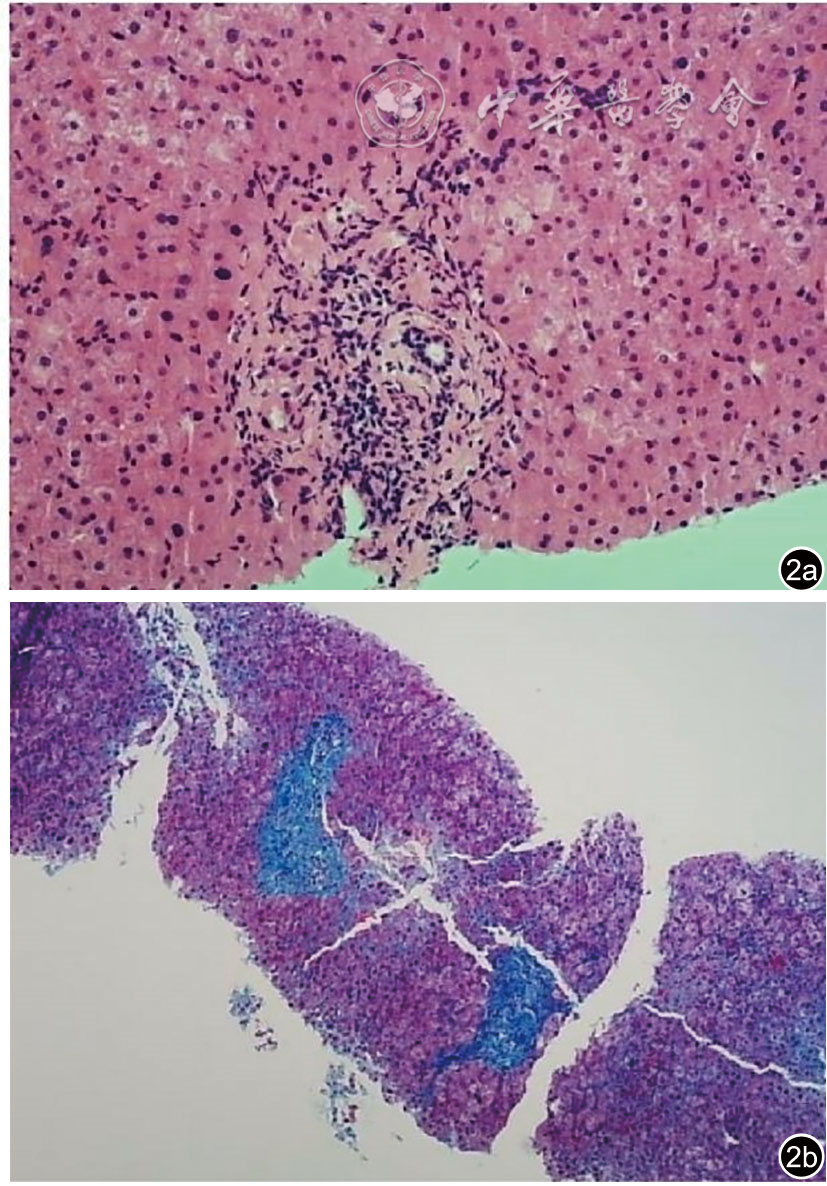

图2 肝穿刺活检病理检查图像。图a示汇管区炎症表现,少量淋巴细胞、浆细胞浸润,局部轻微界面炎。肝细胞轻度水肿、气球样变性,少许点状坏死(HE染色×400);图b示汇管区纤维组织增生从汇管区向周围延伸,形成少量纤维间隔,但未形成完整的肝硬化结构,肝脏结构尚未完全破坏(Masson染色×100)